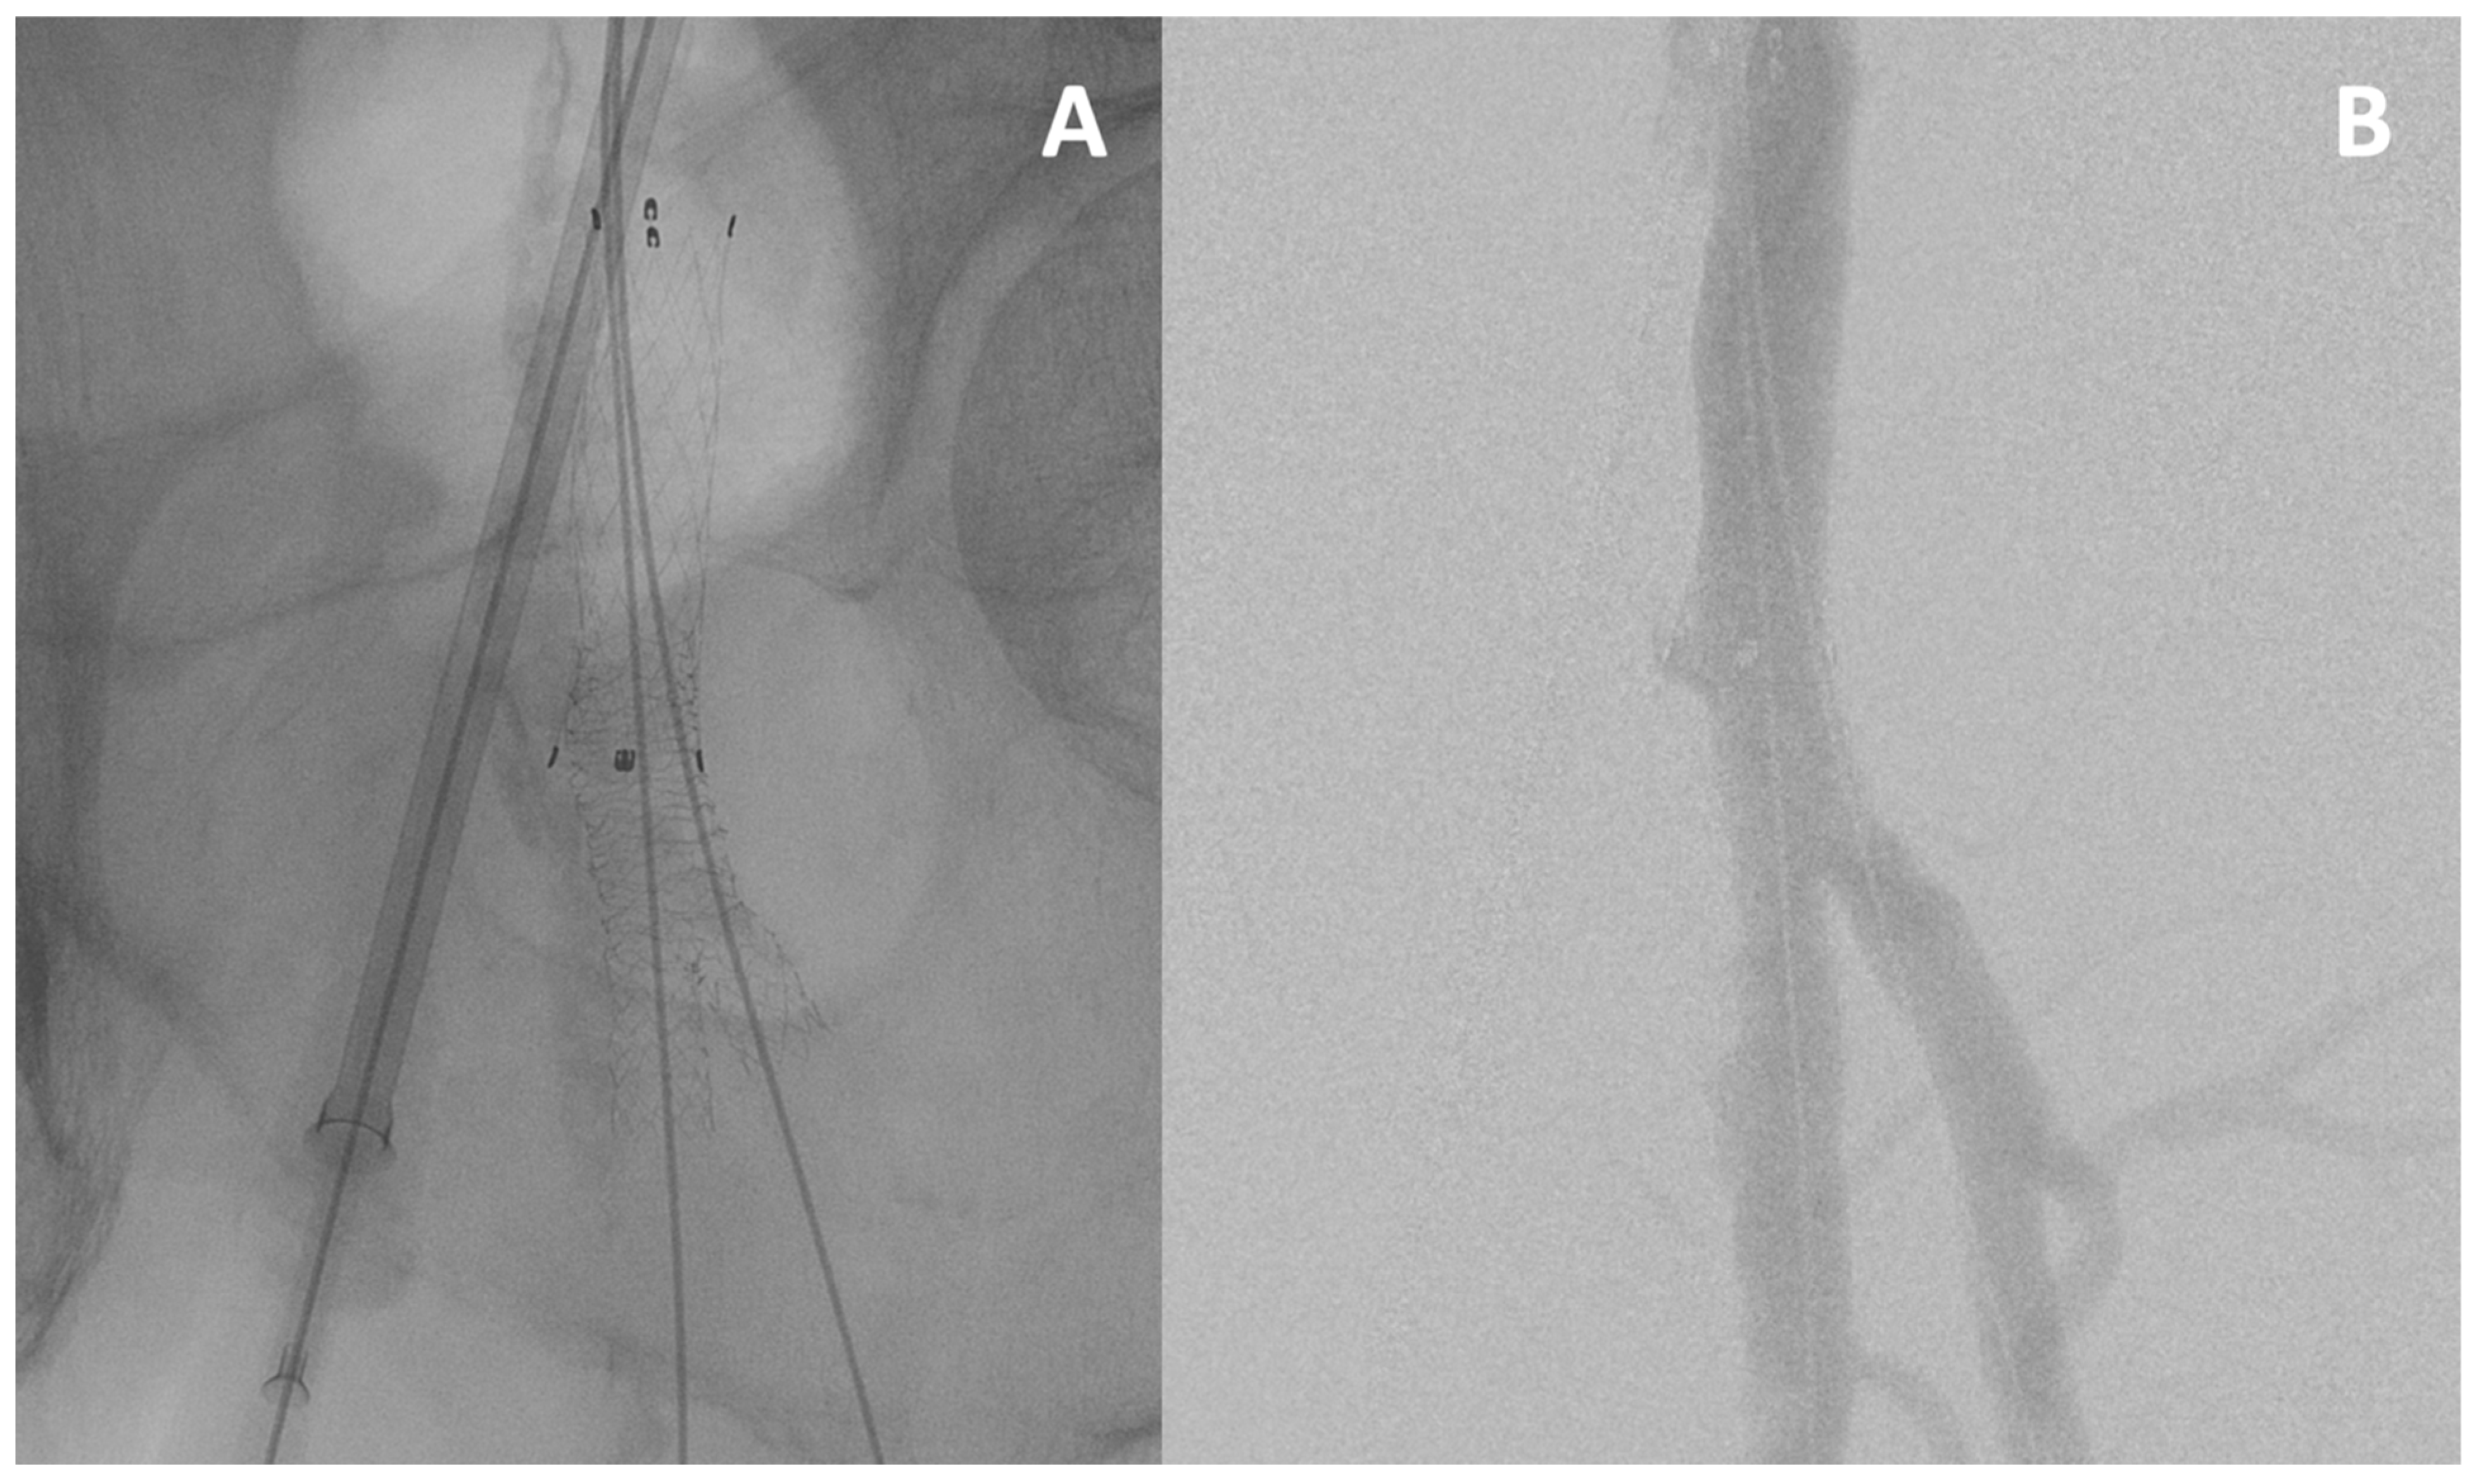

Culotte Technique

This technique allows for the creation of a real bifurcated stent in cases of CFA, DFA, and SFA impairment (Figure 3). It starts with the TAP technique, but the protrusion of the second stent into the first is very important. A POT is performed on the second stent and its struts are crossed to end with a kissing balloon technique.

Figure 3.

The culotte technique. The culotte technique is used for a complex lesion of the common femoral artery and its bifurcation, visible on fluoroscopy (A) and angiography (B).